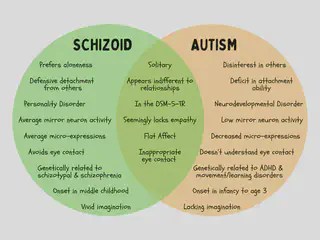

Those with schizoid personality disorder and those with autism spectrum disorder can look similar on the outside at first glance.

But beneath the surface, the two are very different! They have different roots, follow different paths, and carry different outcomes.

Schizoid personality disorder and autism spectrum disorder overlap in their observable symptoms. Externally, others can see both those on the autism spectrum and those with schizoid personalities as lacking empathy, having odd communication, and preferring aloneness, as well as being sensitive, emotionally detached, socially disinterested, and cognitively rigid1 2. In fact, one study found a 26% overlap between Asperger’s disorder and schizoid personality disorder - the highest out of all the personality disorders1. However, both are not “allowed” to be diagnosed in the same person, per the DSM3.

Before we get to genetics, it’s important to remember that schizoid is associated with schizophrenia in the research. We know that schizophrenia has a strong genetic loading with first degree relatives having an eight- to eleven-fold risk5. We also know that there is substantial heritability for autism spectrum disorder3. Yet, autism and schizophrenia do not show up in the same genetic lines2, which means they are genetically separate. Additionally, schizoid personality disorder has higher comorbidity with schizophrenic and dissociative syndromes, as well as other personality disorders such as, avoidant, schizotypal, and obsessive-compulsive syndromes6. In contrast, autism spectrum disorder has higher comorbidity with other neuro- and/or developmental diagnoses such as ADHD, movement disorders, learning/intellectual disorders, and epilepsy3. Put this all together, and there’s a clear delineation between schizoid as a personality style/disorder and autism spectrum as a neurodevelopmental condition.

Because autism spectrum disorder is a neurodevelopmental condition, it most often presents early in childhood, around the age of 2 or 3, or possibly earlier2. (Of note, while it can present in later development or even adulthood, this is the exception and not the rule). Childhood is also where we see a lack of imaginative play and concrete thinking, as well as stereotyped behaviors3. For example, a child may not engage in social behaviors such as reciprocal eye contact, copying (social smile), or turn taking interactions (i.e. peekaboo, babble conversation). They might not engage in pretend play, only play with a specific toy constantly, and engage in repetitive body movements (i.e. toe walking, flapping hands, arching back, head banging).

Meanwhile, schizoid personality traits emerge around middle childhood2, which is approximately ages 6 to 11. In this stage, focus shifts away from primary attachments towards peers and social groups (i.e. classrooms, sports teams, friend groups). For example, a child might be observed to stare off into space daydreaming instead of engaging in a small group activity with peers. They can actually have difficulty figuring out make-believe from reality because of their strong imagination7. They may withdraw from social interaction and prefer solitary activities.

Mirror Neurons & Facial Expressions

I dug into some research about empathy, mirror neurons, and emotional expression and found something super duper fascinating! One study found that patients with schizophrenia indeed had deficits in observable facial expressions, BUT they had appropriate microexpressions8. So they have normal feelings, but don’t express them. They also found that: others who interacted with patients with schizophrenia decreased their own facial expressiveness and felt more negative experiences (which is perhaps why we overpathologize schizo- dynamics)8. Another study found that actively psychotic individuals had increased mirror neuron activity; schizophrenic individuals had average mirror neuron activity; and individuals on the autism spectrum were found to have little to no mirror neuron activity when observing others9. What this means is that those on the schizoid-schizophrenia spectrum don’t lack emotions and empathy at all, they’re just not expressive. In contrast, those on the autism spectrum have social hardwiring that is not intact. This matches with the research that proposes autism spectrum disorder involves more severe impairment and prognosis2.